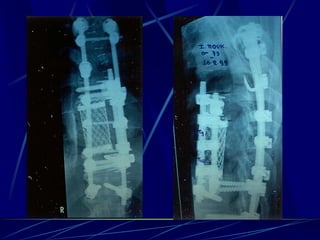

Post-operative infections